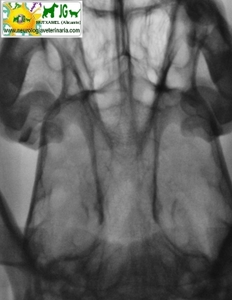

Radiografía digitalizada de cachorro de Siberian Husky con severo trauma craneal |